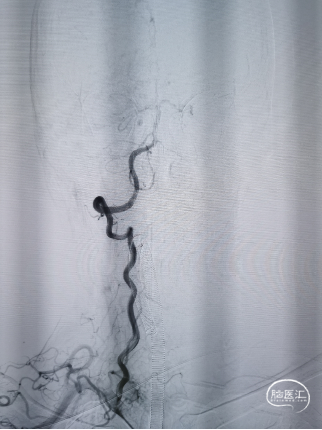

脑血管造影:

脑血管造影可见主动脉弓呈III型弓,左侧颈内动脉及其远端分支良好,前交通动脉未开放。

右侧颈总动脉造影显示右侧大脑中动脉M1段中段闭塞,右侧大脑前动脉通过皮层支向大脑中动脉供血区代偿,代偿晚期可见右侧大脑中动脉M1段远端显影。

双侧椎动脉造影显示双侧椎动脉呈均势型,后交通动脉未开放。